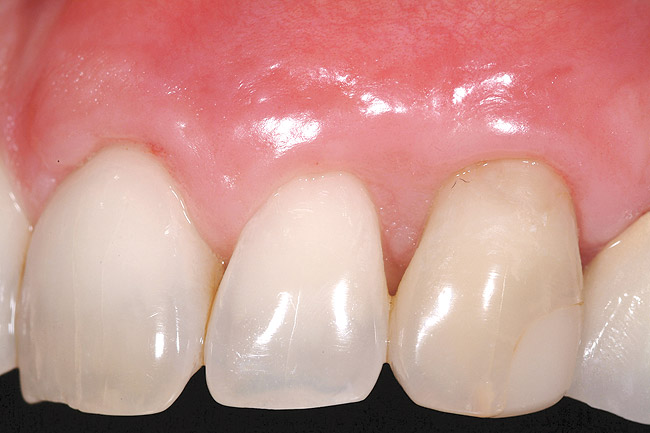

The 2.5-week postoperative clinical view can be seen in Figure 10 through Figure 12. Note the rapid soft tissue healing and maturation. At 6-weeks postoperative, tissue plasty was accomplished to blend the thickened keratinized tissue, in addition to placement of class V composite restorations at teeth Nos. 5, 6, and 11 to create a new restorative margin on the root surfaces.

The 2-month postoperative view can be seen in Figure 13 through 15. Note the color match of the tissue, balance of the facial heights of contour, and zones of attached keratinized tissue present.

Figure 10  Case One The 2.5-week postoperative view, maxillary anterior.

Figure 10

Figure 13  Case One The 2-month postoperative view, maxillary right.

Figure 13

Figure 14  Case One The 2-month postoperative view, maxillary anterior.

Figure 14